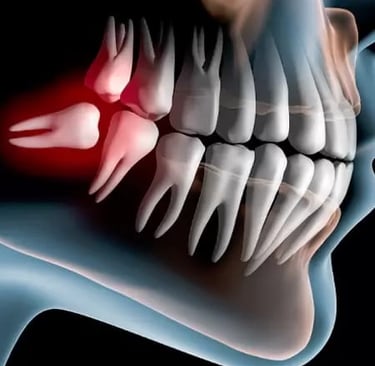

Surgical Extractions & Wisdom Teeth Extraction

Surgical extractions are done for teeth that are broken, impacted, or difficult to remove safely. Wisdom teeth extraction helps prevent pain, swelling, and future dental problems caused by crowded or misaligned wisdom teeth